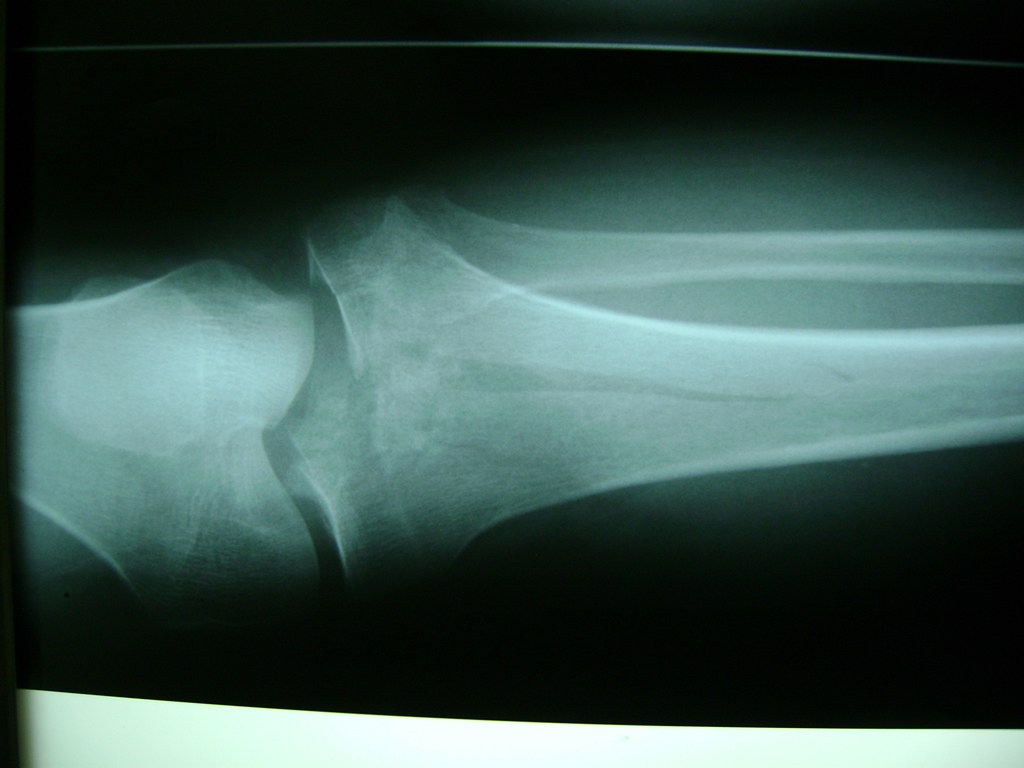

La artroscopia de rodilla es un cirugía en el cual la estructura interna de la articulación es examinada ya sea para realizar un diagnostico o para realizar un tratamiento, este procedimiento se realiza utilizando un instrumento parecido a un pequeño tubo llamado artroscopio.

La artroscopia se popularizo en 1960 y hoy en día es muy común en todo el mundo. Típicamente, es realizada por cirujanos ortopédicos de manera ambulatoria. Cuando se realiza de manera ambulatoria los pacientes pueden regresar a casa después de la operación, no se requiere quedarse en hospital.